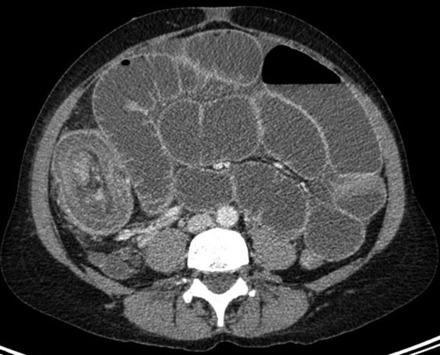

The majority of adult intussusceptions have a well-defined pathological abnormality as the lead point. We present the case of a 41-year-old female who presented to the Emergency Department on four different occasions with intermittent epigastric pain, associated with vomiting. On the fourth occasion, she was found to have a bowel obstruction caused by an ileocolic intussusception, diagnosed on CT. The lead point for her intussusception was a rare non-neoplastic submucosal lesion seldom found in the ileum, an inflammatory fibroid polyp.